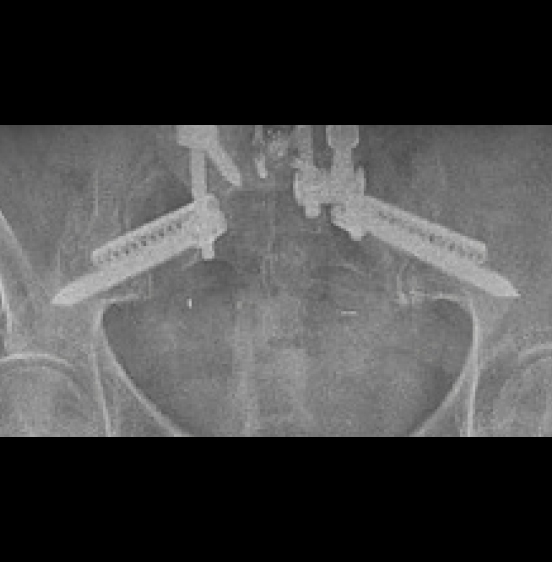

Surgical Treatment:

- T10-pelvis posterior fixation and fusion

- L4 pedicle subtraction osteotomy (PSO)

- Bilateral placement of iFuse 3DTM implants using the Bedrock® technique

- Four points of SIJ fixation

Post-op:

- PI-LL: 43° to 7°, C7-SVA: 24cm to 5cm

- Back and SI joint pain improved post-operatively. Improvement persisted at 2 years.2